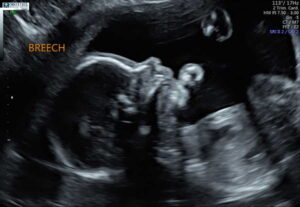

“Cora’s story began in September of 2018 when we first discovered we were pregnant. On November 5th I had a blood test and we found out it was going to be a GIRL! We were so excited to be having our second daughter! On January 31st, 2019, our heart journey began when the radiologist at our anatomy scan said, ‘The heart appears to be abnormal.’ Those words changed our lives forever.

We decided to transfer our care to University of Washington and Seattle Children’s Hospital. The transfer took over 3 weeks to be approved by my health insurance, so at the end of February when we were finally able to be seen, they ruled out the diagnosis of the hernia. We were so happy! She had a chance! We felt so blessed and knew that this was an answered prayer! Over the remainder of my pregnancy, I had countless ultrasounds, fetal echo’s, and non-stress tests. We set my induction date for May 22nd when I would be 39 weeks.